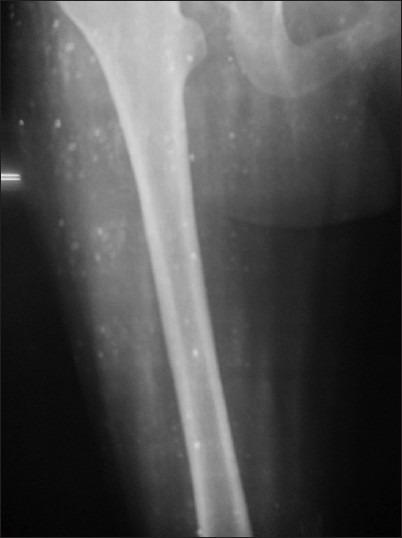

Neurocysticercosis is a common parasitic infection in India presenting usually with seizues, headache, focal neurological deficits. Neurocysticercosis presenting as a psychiatric illness is rare. Disseminated cysticercosis with involvement of central nervous system and head and neck muscles is rare even in endemic areas. We present a case of disseminated cysticercosis, which presented with chronic tension type headache and affective mood disorder. Treatment with cysticidal drugs led to complete remission of psychiatric complaints. In endemic areas history suggestive of mood disorder should not be used as supportive evidence of a primary headache syndome like tension type headche without ruling out secondary causes. Making an early diagnosis can prevent morbidity.